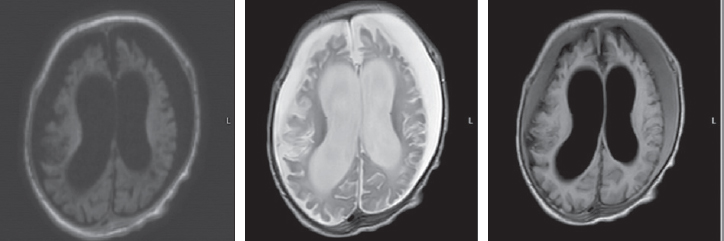

The MRI, performed at seven months of child’s age, revealed a moderate increase in the severity of atrophic changes. Bilateral cystic encephalomalacia of the cerebral hemispheres as well as atrophic hydrocephalus with dilatation of the external and internal cerebrospinal fluid spaces occured. Bilateral chronic subdural hematomas (hygromas) progressed (Fig. 4).

Fig. 4. Magnetic resonance imaging of a patient at the age of 7 months. Axial sections, T1 VI, T2 VI, Flair. There is a bilateral cystic encephalomalacia of the large hemispheres of the brain, atrophic expansion of the external and internal liquor spaces – a moderate increase in the severity of changes. Bilateral chronic subdural hematomas (hygromas) – a moderate increase in fluid volume

Рис. 4. Магнитно-резонансная томограмма пациента в возрасте 7 мес. Аксиальные срезы, Т1ВИ, Т2 ВИ, Flair. Отмечается билатеральная кистозная энцефаломаляция больших полушарий головного мозга, атрофическое расширение наружных и внутренних ликворных пространства — умеренное нарастание степени выраженности изменений. Двусторонние хронические субдуральные гематомы (гигромы) — умеренное увеличение объема жидкости